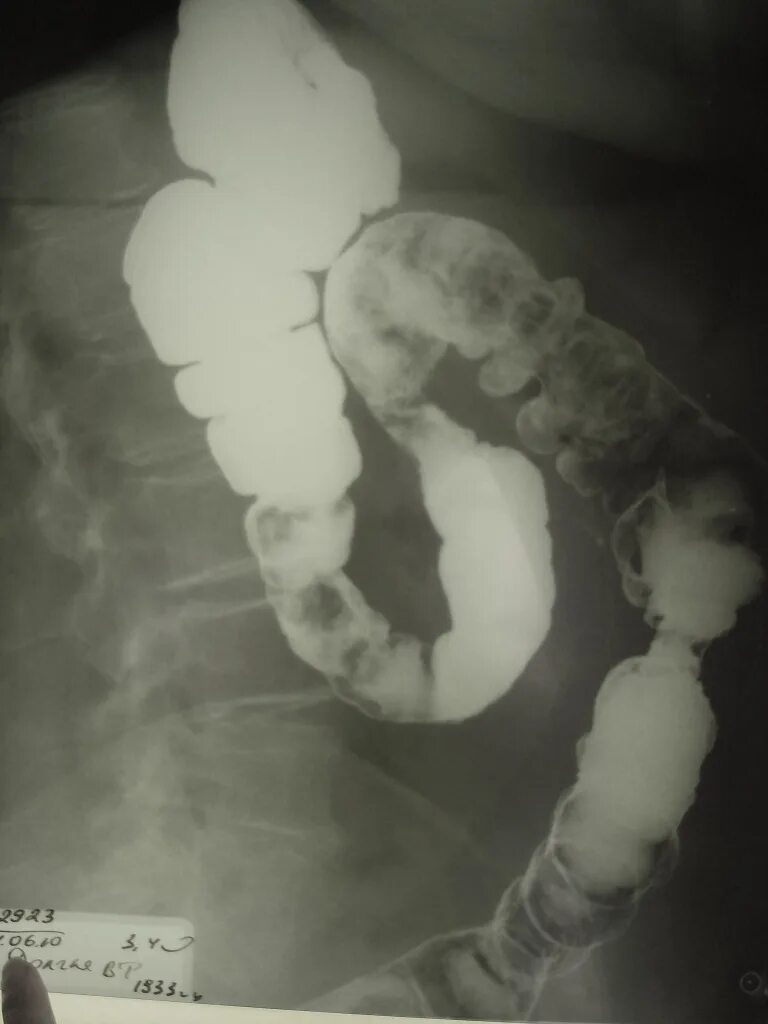

Ирригоскопия выявляет